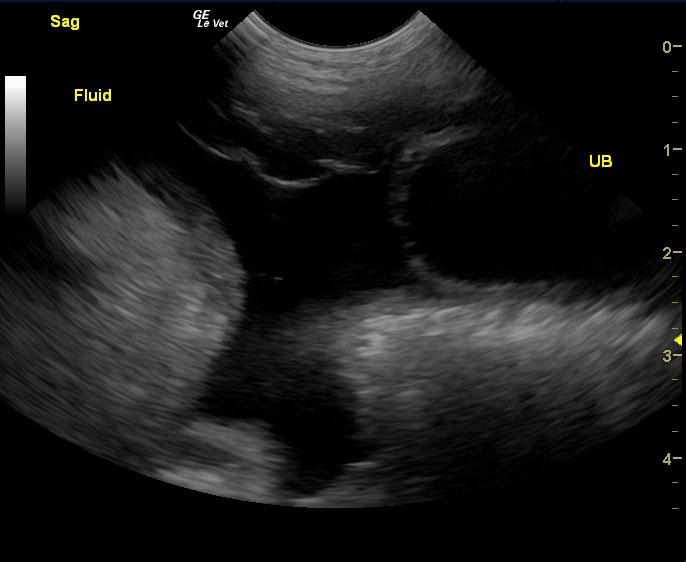

Protein losing enteropathy.

Lymphangectasia type presentation with secondary ascites.

If the ascites is transudate based on abdominocentesis this would be most consistent with protein losing enteropathy and secondary albumin loss, but given that the bloodwork was taken 4 days prior to the sonogram my concern is that the albumin is likely lower than 1.7 at this point. Anything less than 1.5 would justify poor oncotic pressure and free fluid formation. Urinalysis and assessment for concurrent protein losing nephropathy would be recommended. Liver function may also be compromised adding to the albumin loss issue. Plasma transfusion, broad spectrum deworming, calcium supplementation, Purina HA or Royal Canin HP diet, Metronidazole and Prednisone therapy would all be indicated. However, corn oil testing and endoscopy would be ideal for a definitive diagnosis as well as mucosal, gastric and duodenal biopsies.